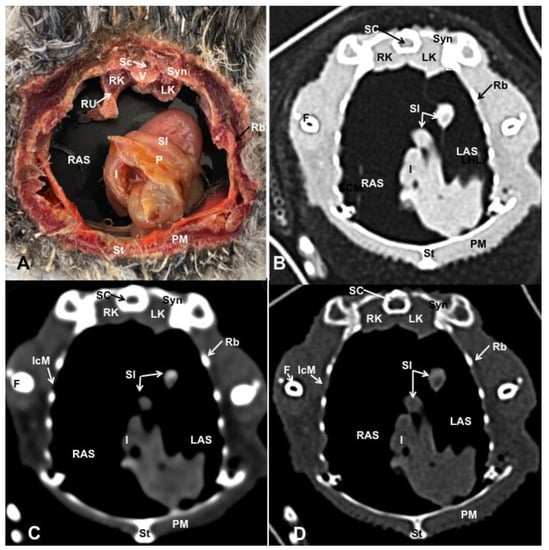

3.1. Anatomical Dissections and Cross-Sections

3.2. Computed Tomography Images